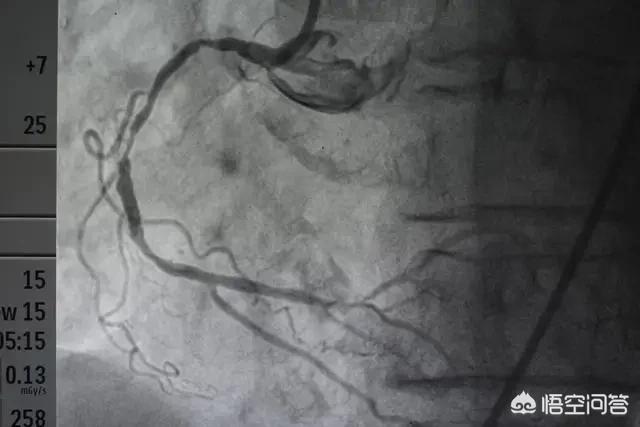

心脏造影做了两个月,有没有放支架呢?按时吃各种药物,后心每天疼怎么回事?

我们心脏造影一般有四种结果:

1、心血管完全正常,排除冠心病及冠状动脉粥样硬化,那么什么药都不用吃。

2、血管狭窄,属于动脉粥样硬化或轻度冠心病,需要长期规律吃药。

3、严重狭窄,需要支架。

4、复杂狭窄,只能搭桥。

如果症状典型,心电图有明确的改变,那么就需要尽快行冠脉造影复查,看看究竟是血管哪里出现了问题。